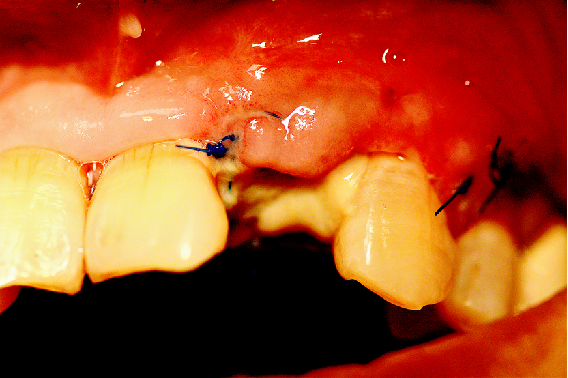

缝合手术切口

瑞拜欧可吸收生物膜具有一定抗菌活性,复合PRF保护,尝试拔牙创开放愈合,保证了龈乳头原位缝合、避免了膜龈联合位置异位,有利于日后的美学效果,术后常规口腔护理、漱口、服用抗生素5天。

术后5天 拆线

牙龈稍显红肿,清洁、无感染迹象,伤口内可见纤维蛋白覆盖。

拆除缝线后牙龈情况。

切口区域上抑菌凝胶,嘱患者常规漱口、口腔卫生维护,勿用力“鼓腮”式漱口。